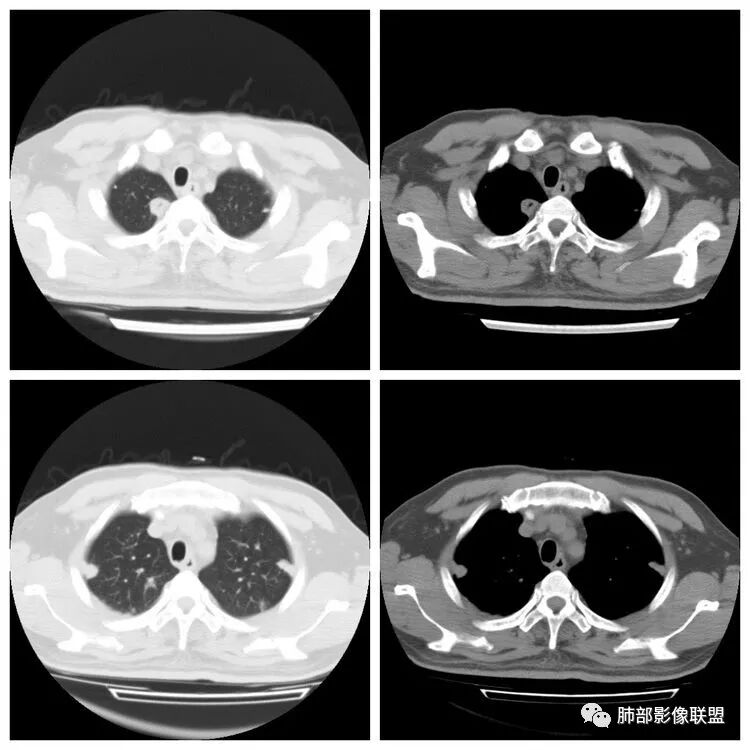

胸 CT

Lotus:不能除外肺炎克雷伯三生石上:考虑真菌丽:双肺胸膜下散在结节状及斑片状高密度,密度不均,伴反晕征,首先考虑炎性病变,曲霉菌可能大Shelia:双肺多发结节,大片实变还有胸膜下楔行影,以胸膜下分布为主,有晕和大反晕,左肺实变区有空洞空泡,叶间裂下坠,结合病史,考虑感染,支持血源性感染,说明病原菌有嗜血管,结合肝内病灶,会不会是真菌合并细菌感染,毛霉或曲霉合并肺克?THINKER:急性起病,2DM,蛋白低,CT:双肺多发结节`斑片影,胸膜下为主,伴反晕征,与血管关系密切,考虑血源性,CT肝低密度,首选糖尿病→肝脓肿→肺克,鉴别毛霉。

王秀仙:双肺多发结节及结块影,边缘清晰,呈反晕征,左肺上叶大片实变,密度不均,下缘膨隆,其内可见残留肺组织,肝脏可见低密度,考虑肺克。鉴别毛霉。崇军:高热,感染症状,影像多发结节,反晕征明显,糖尿病,真菌放在第一位,杰克金毛,毛霉菌可能。Yiren Sishui(厶水伊人):肺克,鉴别毛霉菌感染;一米阳光:中年男性,急性起病,双肺散在结节状及斑片状高密度影,以胸膜下明显,没有坏死,密度不均,考虑血播来源,肺克可能,鉴别,金葡,曲霉毛勤香:双肺多发结节斑片状影,呈反晕征,左肺上叶舌段大片状影,叶间裂下坠,糖尿病患者,急性起病,考虑感染性变,首先肺克,代排真菌类曲霉毛霉等,肝脏也有病灶,一元论。小景:糖尿病、肝脓肿?肺内多发结节,反晕,与血管关系密切。考虑肺克。

南边:胸膜下,类圆形,边界清,内有坏死,典型的反晕征,支气管壁增厚不明显,支持血道来源脓毒栓子所致梗死、感染

血道来源没问题

左下叶大片类似病灶

南边:反晕征是毛霉菌的特点按理单从影像:毛霉菌更多符合因为细菌性的特点:液气平面,囊,这个没出现

肺克的影像表现(唐绍宏总结):分布:单侧上叶病变,以右肺上叶多见;患者长期卧床则双脚下肺后基底段分布(国外下肺多见,可能与平均寿命长,卧床及住托老机构多有关) ;如多叶段病变,则以肺上叶后段或下叶后基底段为最明显形态:气管壁增厚、磨玻璃、小叶实变、节段实变、大叶实变,坏死小空洞(直径小于2cm) ,少量胸腔积液50%、脓胸20%特点:早期气管壁增厚较明显、广泛,越靠近病灶越明显,越靠近肺门越明显,见于实变病灶外,偶尔见于磨玻璃影内(支气管通气征) ;未经抗生素治疗,实变病灶内无支气管通气征;早期即可出现坏死,无论坏死还是空洞,绝大多数直径小于2cm (可能与此菌有厚夹膜有关,参考隐球菌)